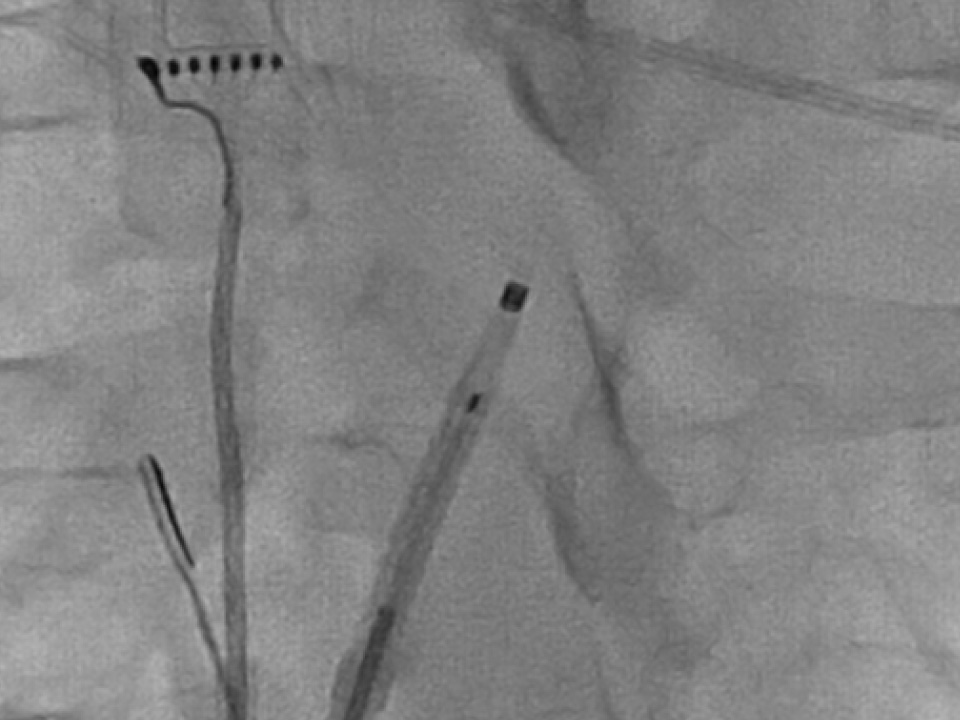

Radiopaque marker of NRG Transseptal Needle during fluoroscopy.

Visualize the RF needle

Locate the RF needle on your mapping system. Visualize the tip’s exact location with a radiopaque marker during fluoroscopy.